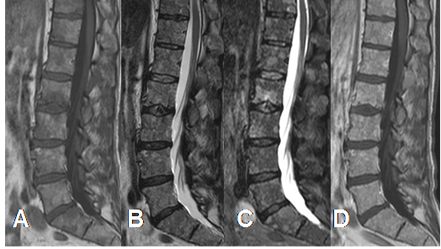

Fig 196. Mieloma.

A: Rx lateral. Osteoporosis generalizada, sin lesiones focales.

B: RM sagital en T1 y C: RM sagital en STIR. Completa reconversión a medula roja en los cuerpos vertebrales, con lesión focal y aguda en D12.